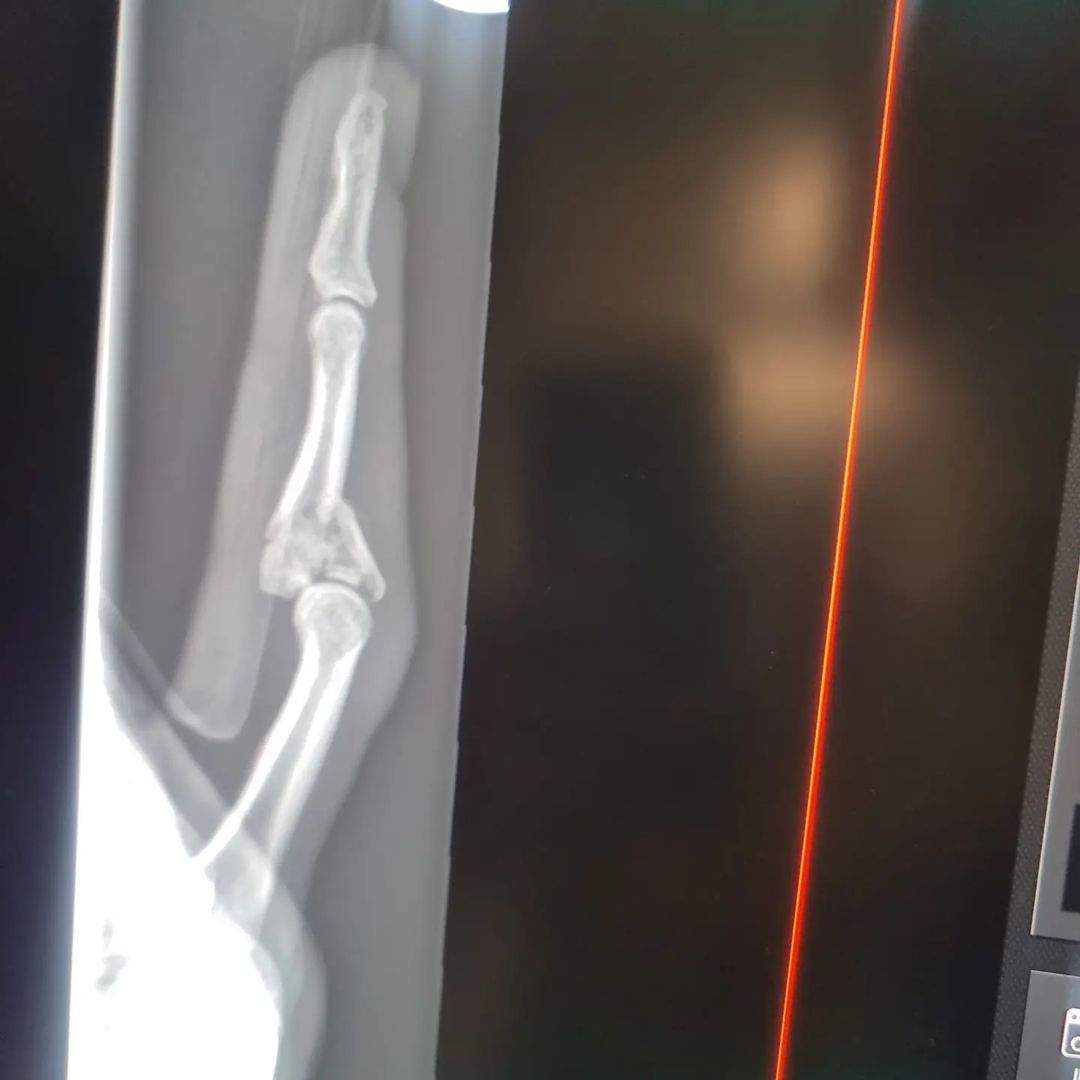

Sorry ive been out of action for a while guys. Broke my finger and I'm still repairing until the end of August. Thanks for being so patient. Will be back very soon. Thanks for all the love and support always xx

#brokenfinger #shatteredknuckle #fellover #mua #makeupartist #injured #xray